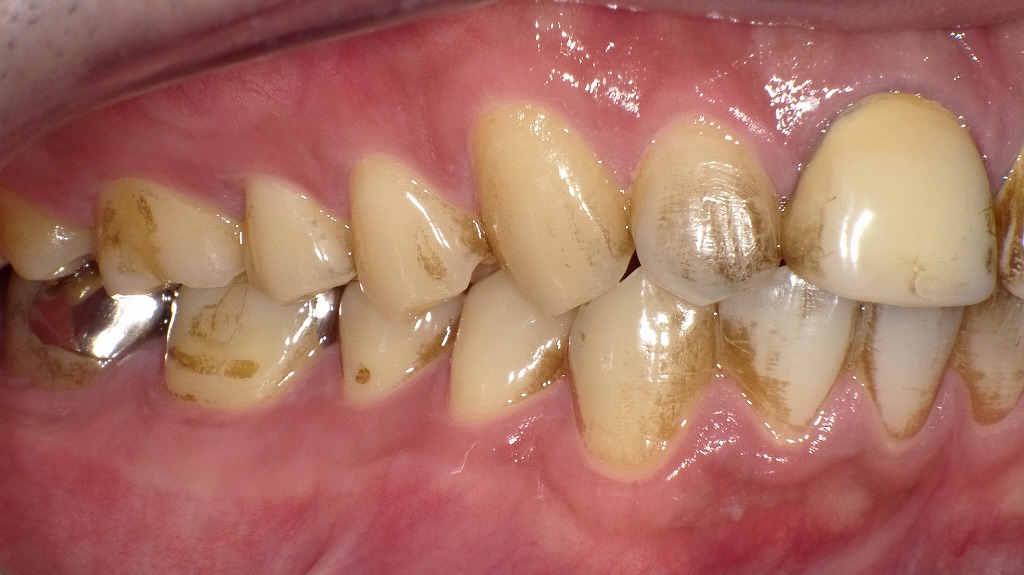

💨エアフローによる歯のクリーニング施術例

エアフロー施術前

ステインが大量に付いています。通常の歯磨きではなかなか落ちません。